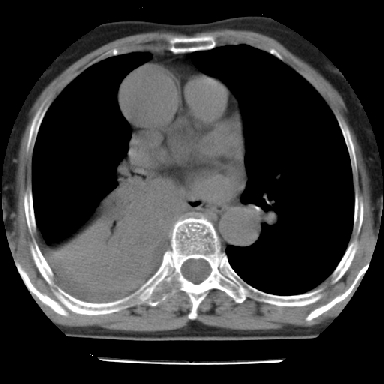

以下是引用苯小孩在2007-4-13 16:20:00的发言:[br]1、右下肺中央型肺癌并阻塞性肺不张、肺内转移、胸椎右侧附件亦有转移<横断层面第8层>.[br]2、右侧胸腔积液.

以下是引用swyyy2007在2007-4-13 15:31:00的发言:[br]右肺门下区肿块,右肺下叶支气管阻塞,右肺下叶不张,右侧大量胸腔积液,右肺中叶见结节状高密度影,边缘清,纵隔内见肿大淋巴结。首先考虑右下肺中心型肺癌伴右肺下叶不张、中叶、纵隔淋巴结转移。右侧胸腔积液。